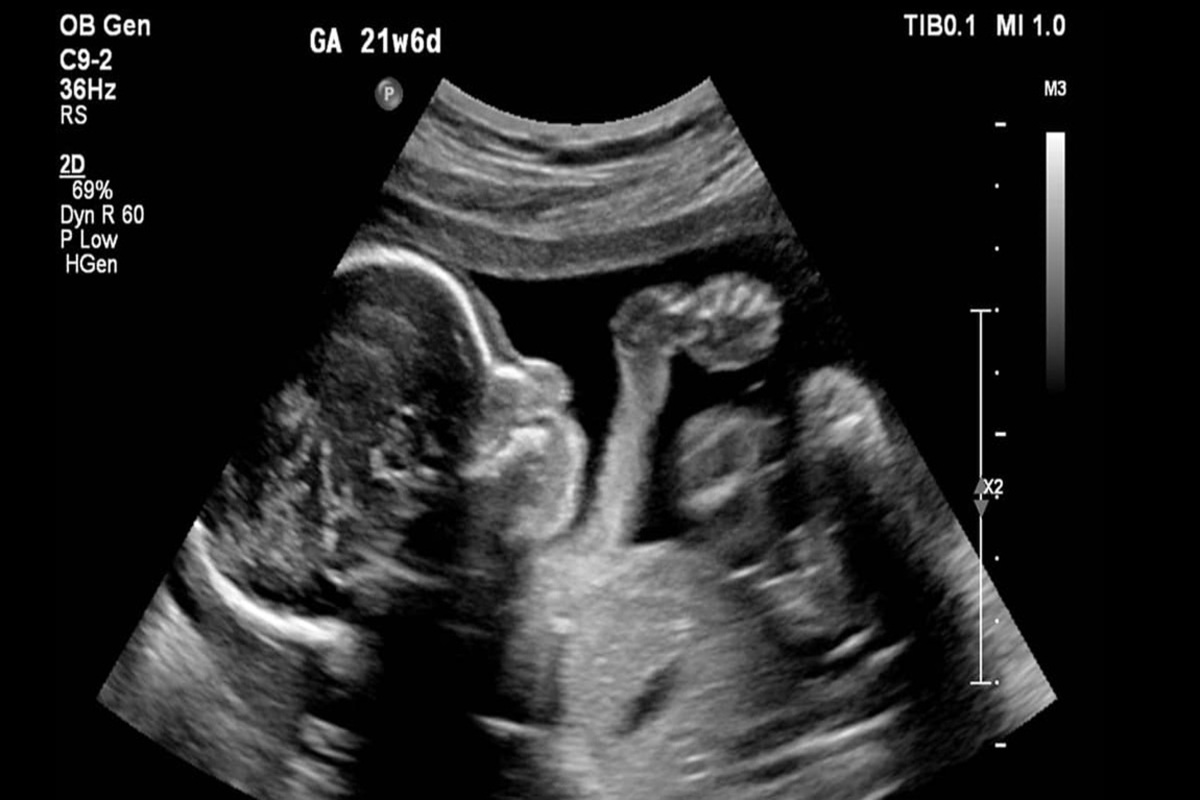

کیهان: زنان با چه استدلال هایی حاضر به سقط جنین می شوند؟

کیهان نوشت: بر اساس پژوهشی که پژوهشکدة علوم بهداشتی جهاد دانشگاهی انجام داده، به دست آمده که مشکل مالی و اقتصادی، اختلاف با شوهر، جنسیت جنین، فاصلة کم بین بارداری‌ها، سن کم مادر، سن بالای مادر، تعداد زیاد فرزندان، گرفتاری شغلی مادر، اعتیاد شوهر، بارداری در ابتدای ازدواج یا در دوران عقد و... از عواملی هستند که در بارداری ناخواسته، سبب می‌شوند که مادر تصمیم به سقط جنینش بگیرد.

این دلایل موجب می‌شوند که برخی مادران، به خود حق بدهند و خود را قانع کنند که جنینشان را سقط کنند و معمولاً هم تنها چیزی که ذهنشان خطور نمی‌کند یا جدی نمی‌گیرند، نگاه شرع مقدس اسلام به این عمل است؛ در حالی که از دیدگاه فقه شیعه، سقط جنین از روی عمد، حرام است و در این حکم، اختلافی میان آنها نیست و فرقی هم نیست بین این که جنین از راه مشروع ایجاد شده باشد یا نامشروع؛ همچنین بنا به اجماع فقها در حرمت سقط جنین، فرقی میان مراحل مختلف جنین نیست؛ بنابراین، پس از انعقاد نطفه و استقرار نطفه در جدار رحم که مبدأ رشد جنین است، سقط آن حرام می‌شود.

سقط جنین، خواه قبل از دمیدن روح در جنین باشد یا بعد از آن و خواه با رضایت والدین باشد یا بدون رضایت آنها، در همة این حالات حرام است. البته ناگفته نماند بعضی فقهای شیعه سقط جنین را در مواردی مجاز دانسته‌اند مثل موردی که سلامتی مادر در خطر باشد یا جنین ناقص باشد و...؛ اما همین موارد مجاز هم بی‌در و پیکر و بی‌قاعده و ضابطه نیست؛ شروط متعددی باید در کار باشد تا چنین کاری مجاز شمرده شود.

متاسفانه باید اعتراف کرد که اتفاقی که کم و بیش در جامعة ما افتاده این است که قبح این کار تا حدی شکسته شده و مثلا برخی از مادران با خود می‌گویند: «شکم خودمه، بچة خودمه اختیارش رو دارم؛ تازه هنوز هم همچین بچه نشده، کسی هم متوجه نمی‌شود، پس به کسی ربطی ندارد».

همین مادران را اگر بگویی بچة دو ساله‌ات را ببر توی آشپزخانه با چاقوی گلویش را ببر، حیرت‌زده و ناراحت و می‌گوید مگر من «جانی»ام؛ در حالی که جانی، جانی است و فرقی نیست بین اینکه محل ارتکاب قتل، شکمت باشد یا آشپزخانه‌ات. نشان به آن نشان که در سقط جنین غیرشرعی باید دیه داد و حتی طبق نظر بعضی فقها، گاه قصاص ثابت می‌شود.